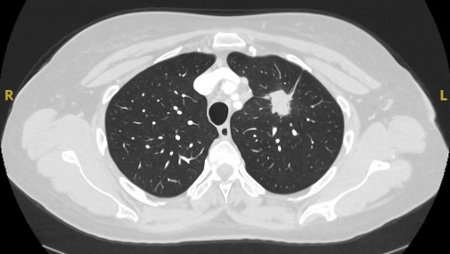

Computed tomography (CT) showing a right upper lobe spiculated solitary nodule within emphysema, in a current smoker with previous asbestos exposure. Note the visible pleural plaque on the left side. Resection histology revealed adenocarcinoma of the lung

From the collection of Dr George Tsaknis, MD, PhD, FRCP(London), MRQA, MAcadMEd, PGCert; used with permission